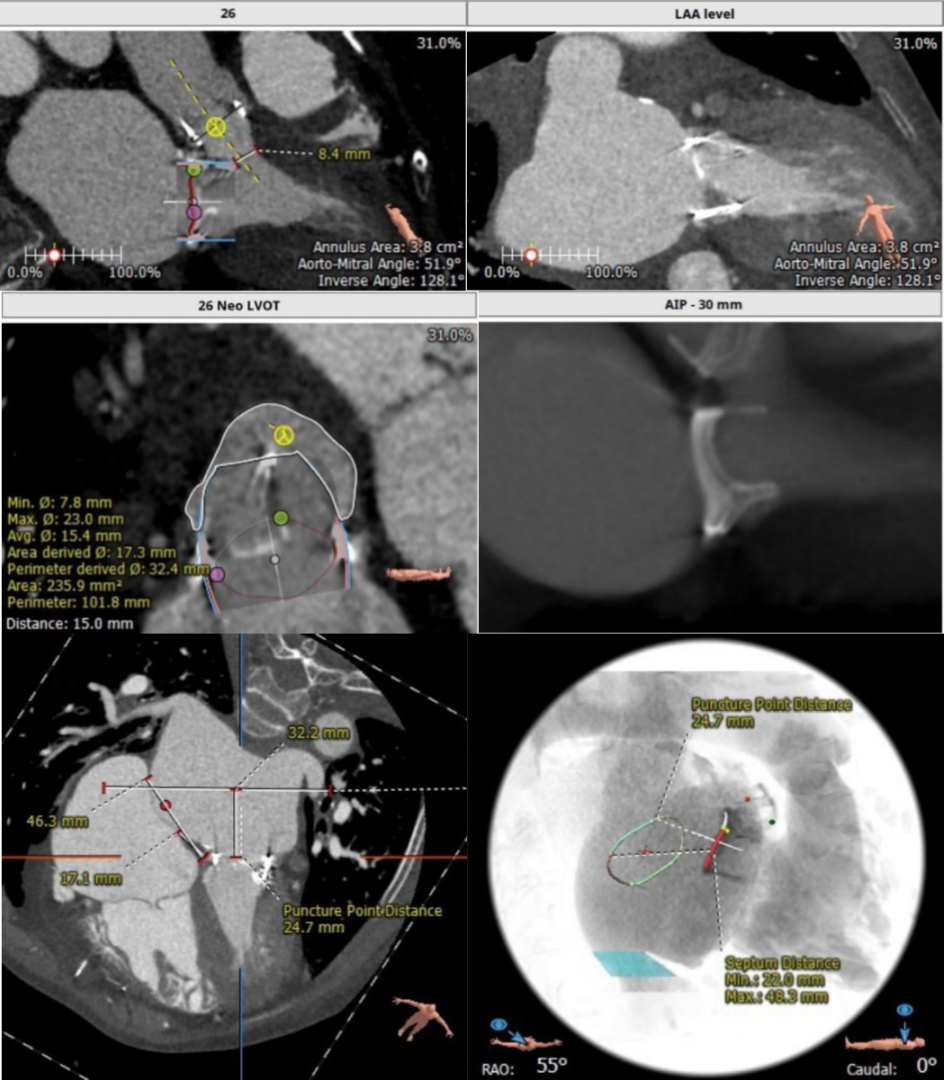

二尖瓣瓣中瓣CT评估

经过充分的术前食道超声及心脏CTA的评估,团队一致选择目前国际上瓣中瓣(Valve in Valve)技术使用最多最成熟的器械——Edwards SAPIEN3瓣膜。与林阿姨及其家属充分沟通后,在经验丰富的王焱院长的指导下,珠海市人民医院结构性心脏病团队决定为林阿姨同期进行主动脉瓣及二尖瓣的双瓣膜置换,采用的方案是先经股动脉途径为其行主动脉瓣的瓣中瓣植入(VinV TAVR),然后经股静脉途径,穿刺房间隔后,行二尖瓣的瓣中瓣植入(VinV TMVR),视情况对房间隔穿刺后的缺损进行封堵。